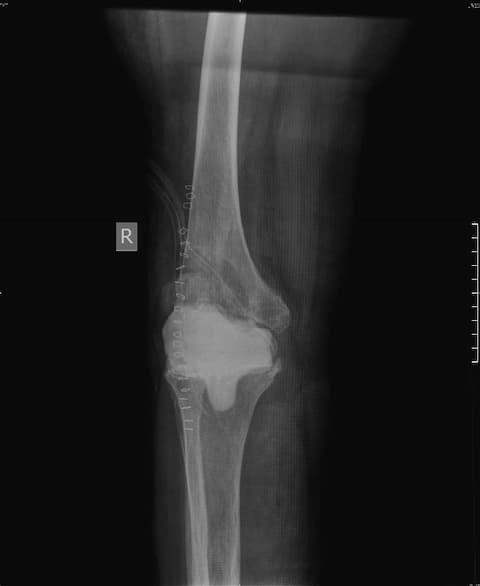

Үе дайрсан ясны анхдагч хавдар, ясны дутмагшлын үед хийгдэх мэс засал image3

Зураг1. Зүүн дунд чөмөгний түнхний үе орчмын ясны хавдар